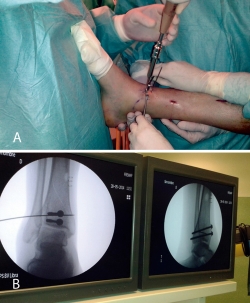

3. Fractura de tipo C: reducción artroscópica, fijación de la epífisis con tornillos canulados y fijación final de la epífisis a la diáfisis por técnica MIPO.

En este caso, es esencial observar las Rx con y sin tracción que nos indican cómo se va a comportar la fractura. Si la fractura es reductible en tracción, es muy probable que podamos realizar una osteosíntesis con restitución completa de la superficie articular. Al realizar la TC, apreciamos la disposición de los fragmentos para marcar una estrategia de reducción bajo control radioscópico y artroscópico, y colocación de los tornillos canulados que fijarán la epífisis distal de la tibia.

Posteriormente, colocaremos la placa en la tibia por vía MIPO realizando una incisión interna, separando la vena safena y deslizando la placa que se fija de manera provisional. Tras comprobar por radioscopia la buena posición del implante, se realiza la fijación definitiva con los tornillos que consideremos adecuados. En el caso de que tengamos que usar un fijador, este sustituye a la placa interna (Figuras 17 a 20).

Figura 19. Colocación del tornillo en el Tillaux con la extremidad en tracción y posteriormente la placa MIPO (minimally invasive plate osteosynthesis).